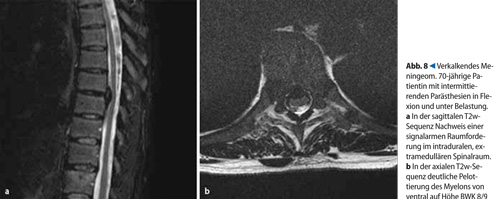

Sie besitzt die höchste Sensitivität zum Nachweis tumoröser und entzündlicher Prozesse und wird zur Klärung von Ausbreitung und Beziehung fraglicher Raumforderungen zu den intraspinalen Strukturen eingesetzt als auch zum Staging und zu Verlaufskontrollen primärer Wirbelsäulentumoren. Eine Zuordnung der intraspinalen Raumforderung zu einem der drei Kompartimente extradural, intradural-extramedullär oder intradural-intramedullärwird in der Regel erst durch die MRT ermöglicht (s.Tab. 4,. Abb. 7, 8).